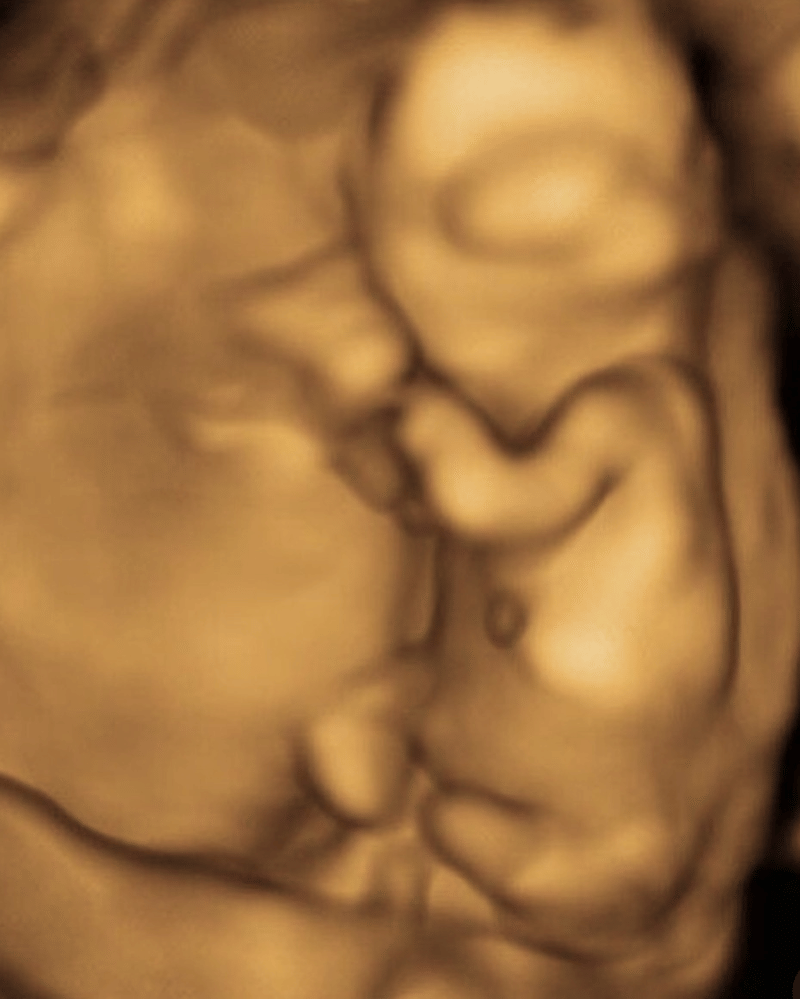

Tak menunggu lama, Putri Habibie mengumumkan kehamilan anak pertamanya pada Oktober 2025 melalui media sosialnya.

Usia kehamilan Putri Habibie diperkirakan sudah 4 atau 5 bulan.

Hanya selang beberapa bulan dari pernikahannya, Putri Habibie kini sudah mengumumkan kabar kehamilan anak pertamanya.

Melalui media sosialnya pada Selasa, 8 Oktober 2025 lalu Putri Habibie mengumumkan kehamilannya dengan mengunggah sebuah foto yang memperlihatkan dirinya dan sang suami yang memamerkan hasil test pack.

3. Usia kehamilan Putri Habibie diperkirakan sudah 4 atau 5 bulan

Putri Habibie belum mengatakan secara pasti berapa usia kehamilannya saat ini, namun diperkirakan jika kini kehamilannya sudah masuk trimester kedua di bulan ke-4 atau bulan ke-5.